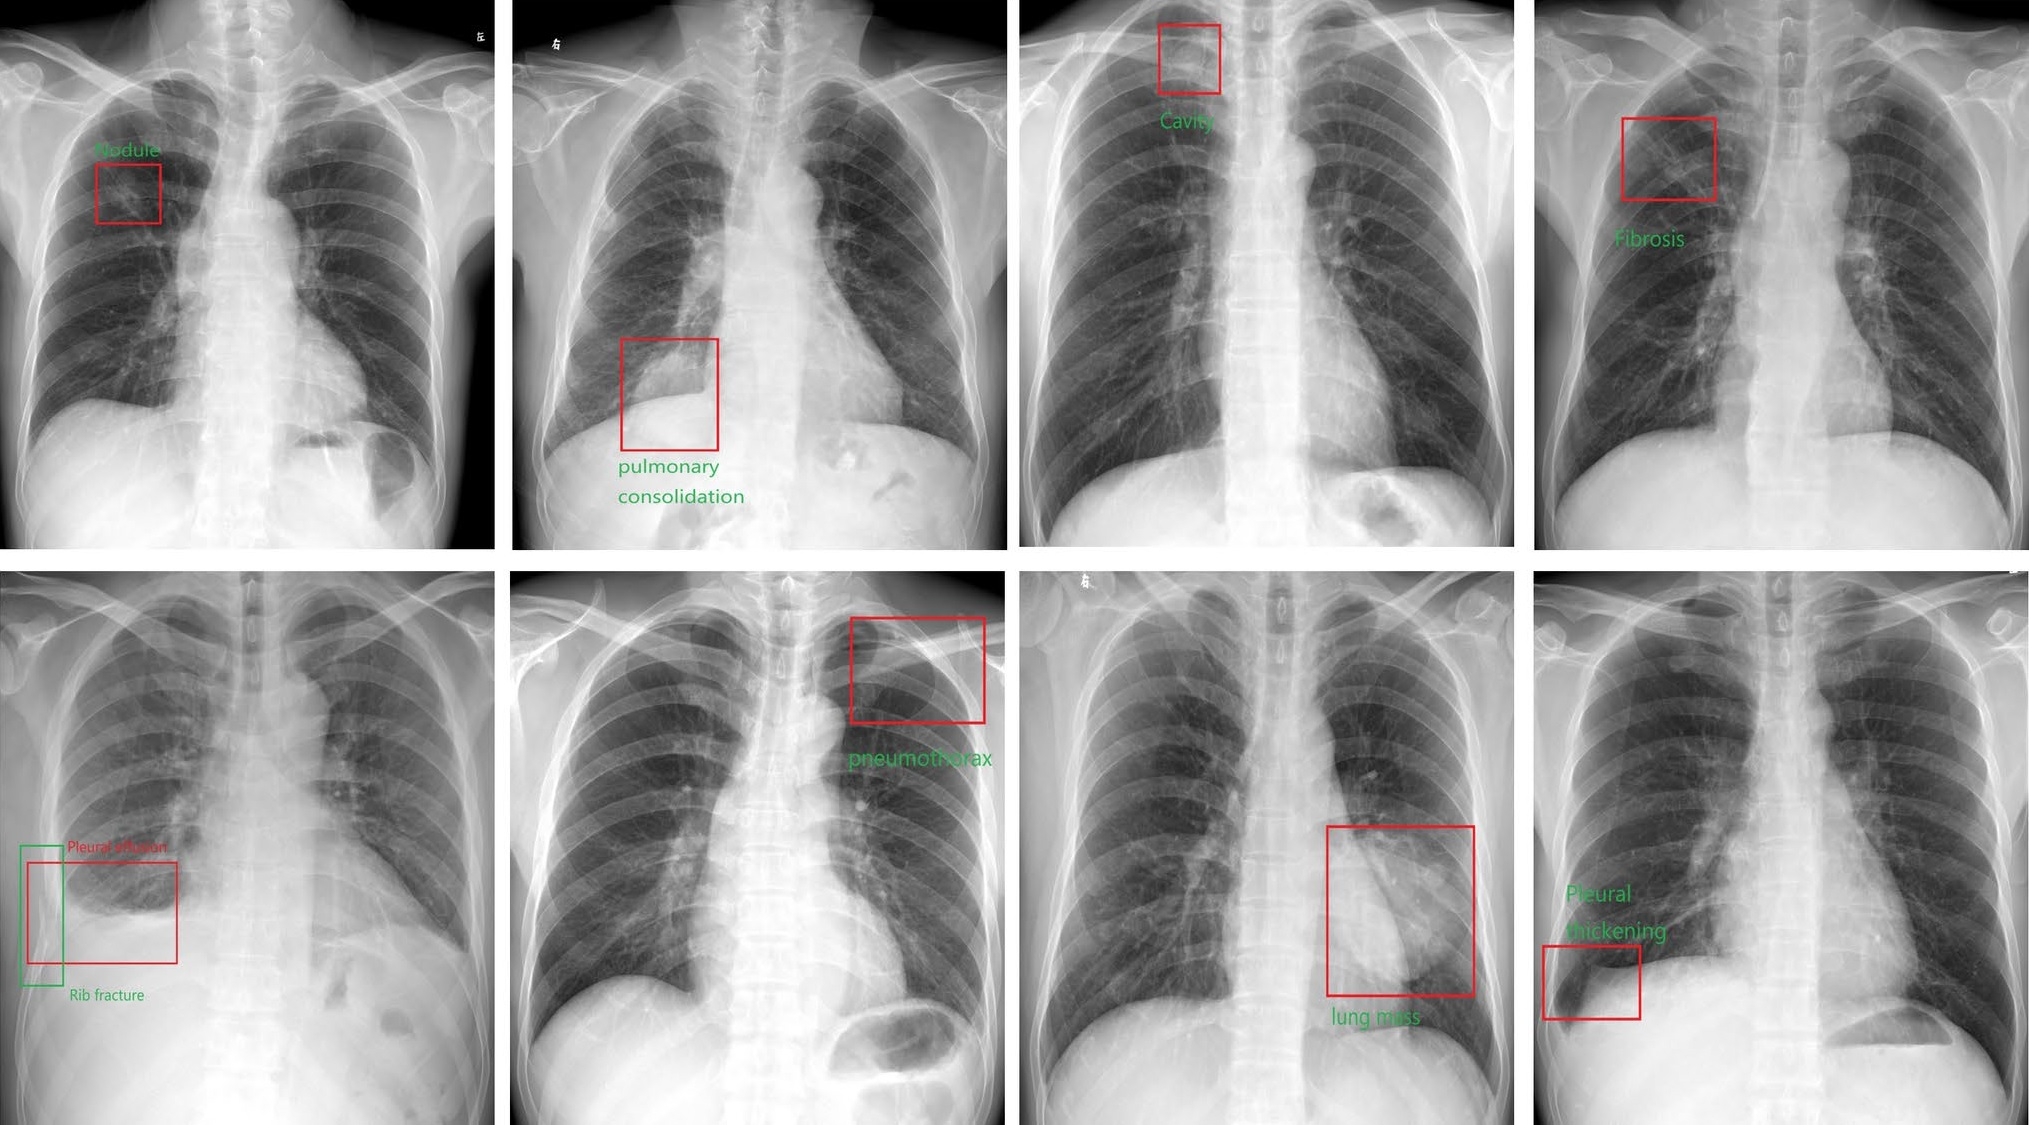

Established tests for achalasia include high-resolution manometry, esophagogastroduodenoscopy, and barium swallow tests. Alternatively, plain chest x-rays can capture several characteristic signs of the condition, such as air-fluid level, opacity, and air esophagogram around the mediastinum, the researchers noted.

To explore whether an AI model could be a useful screening tool for the condition, the group trained a deep-learning AI model using 207 chest x-rays from 144 patients with esophageal achalasia and 240 chest x-rays from age- and sex-matched individuals without it. The diagnostic capability of the AI model was then verified using a test dataset consisting of 17 chest x-rays from 17 patients with esophageal achalasia and 64 chest x-rays from patients without.